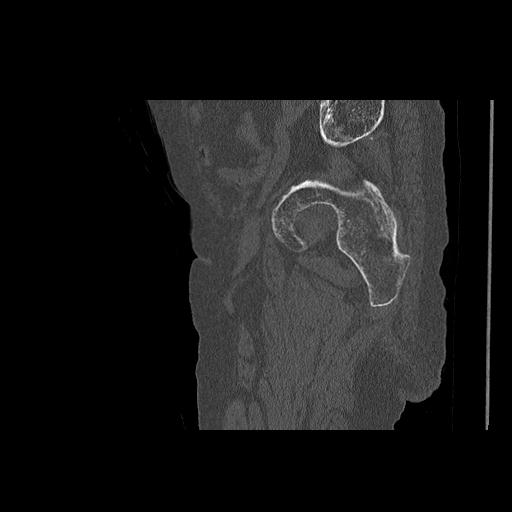

110286 2/17 股関節 2R 74歳女性 右人工骨頭

102903 股関節 2R 1/28 +股関節 2R 1/29 78歳女性 左人工骨頭

82084 1/14 1/20 股関節 2R 78歳男性 右人工骨頭

91569 3/25 両股正面とラウエン 70歳女性 人工骨頭+バンクーバー